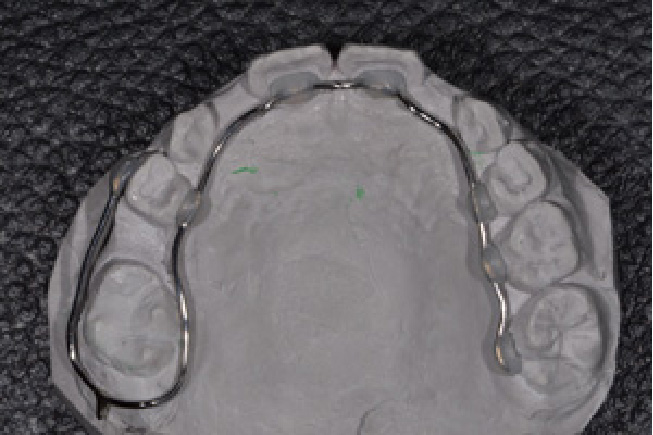

• 予防矯正

歯並びの改善や、筋機能改善(適応年齢3~17歳程度)

歯ならびだけでなく、口の周りや舌の筋肉の機能の改善。正常な成長発育を促す予防的な矯正治療。

【自費診療:プレオルソ:55,000円、交換:11,000円、 床矯正、その他装置 77,000円~】

• 器具イメージ2

• 器具イメージ3